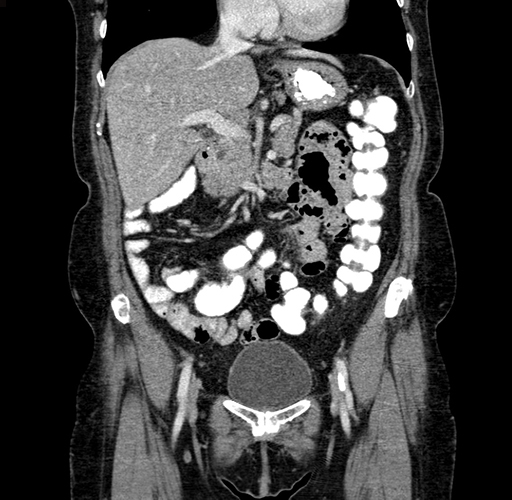

Pre-Chemo: Coronal Venous

Coronal Venous